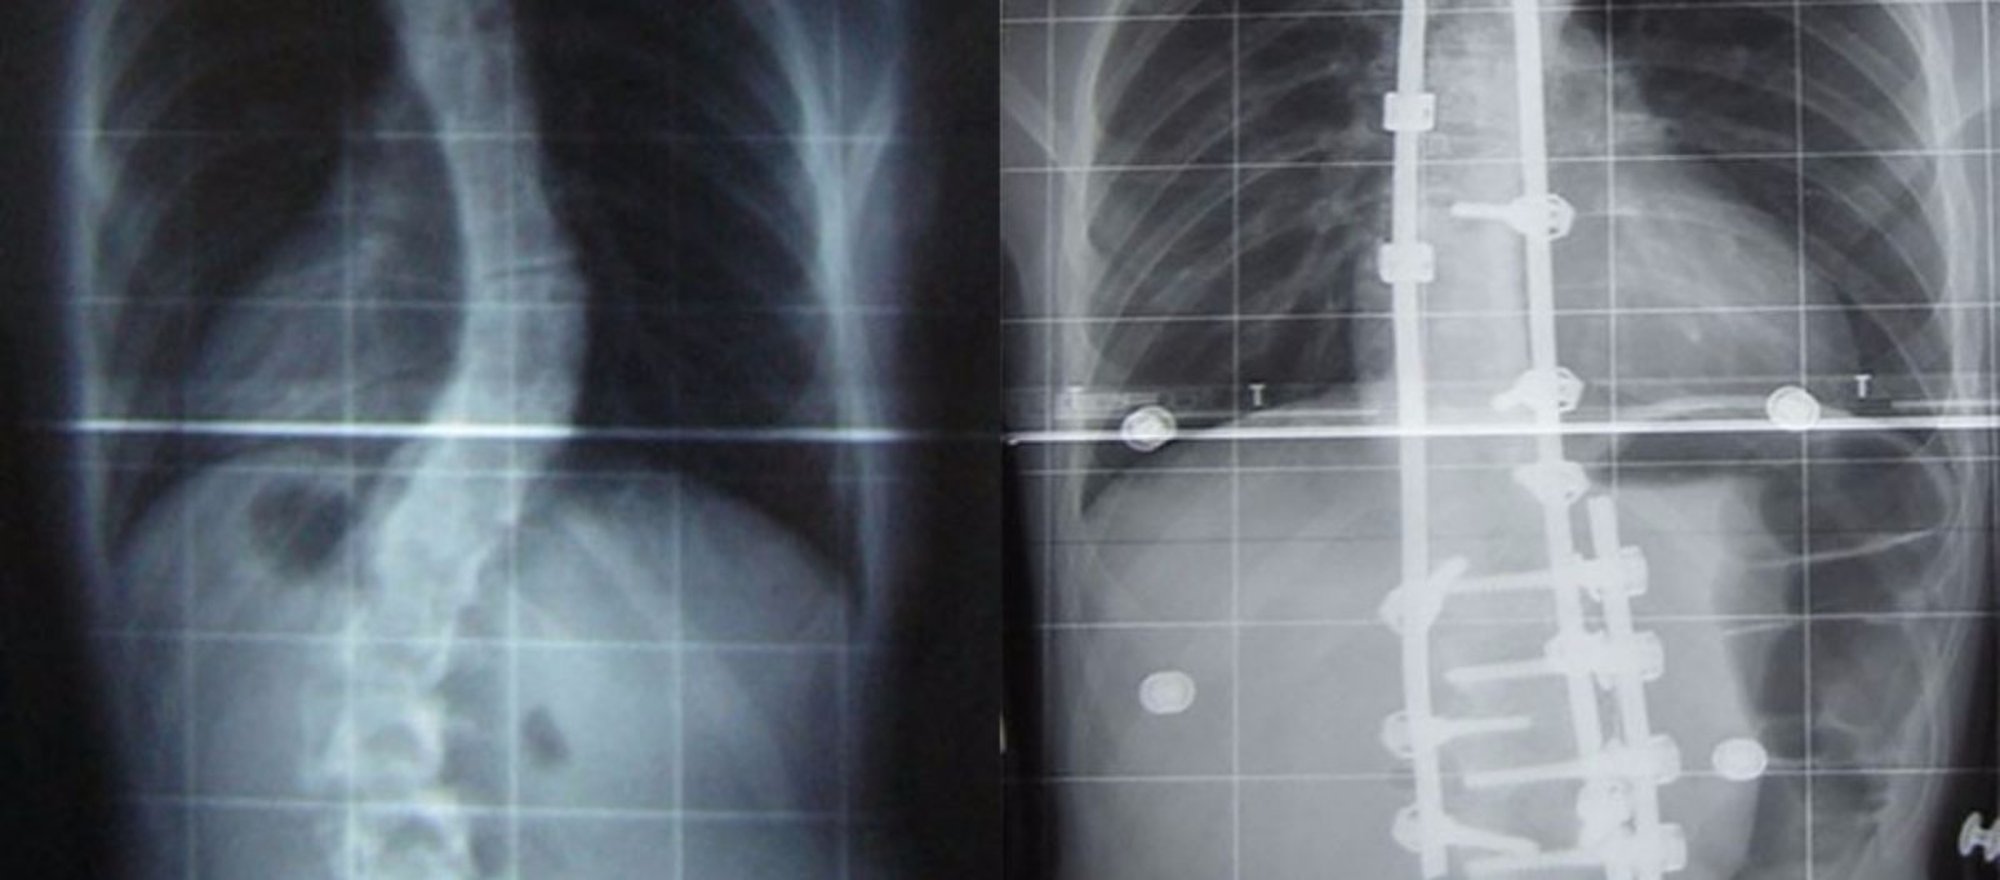

Skolyoz, yani omurga eğriliği, adından da anlaşılabileceği üzere gelişimsel olarak bir insanın omurgasının yamuk/eğri olması hastalığıdır. Aslında omurgamızın doğal bir kıvrımlı yapısı vardır; ancak "normal" şartların ötesine geçecek düzeyde, genellikle 3 boyutta da (en, derinlik ve uzunluk) meydana gelen kaymalar, omurganın şeklini bozar ve sorunlara neden olur. Fotoğrafta, sağ tarafta görülen budur.

Skolyoz çoğunlukla doğuştan gelen bir hastalıktır; ancak idiyopatik olarak, yani bireyin yaşantısı içerisinde rastgele bir şekilde de meydana gelebilir. Kimi zaman Chiari malformasyonu gibi bazı hastalıklara bağlı olarak da oluşabilir. Her ne kadar fotoğraftaki gibi ekstrem vakalar sorunlara neden olabilecek olsa da, skolyozun en yaygın çeşidi olan "geç başlangıçlı idiyopatik skolyoz" tedavi bile edilmese sıkıntı çıkarmayan bir hastalıktır; hatta kimi zaman kendiliğinden düzelebilmektedir. Eskiden bu daha kısıtlı eğrilikler bile düzeltilmezse, yaş ilerledikçe bunların artarak sıkıntı yaratacağına inanılıyor olsa da, güncel çalışmalar skolyozun bu şekilde gelişmediğini göstermiştir.

Eğer ki fotoğraftaki gibi uç vakalar (eğriliğin 45-50 dereceyi aştığı vakalar) söz konusuysa, genellikle ameliyatla tedavi önerilmektedir. Bu da bizi sağ taraftaki fotoğrafa getirir. Sağdaki fotoğraf, soldaki gibi bir bireyin ameliyat sonrası omurgasının düzeltilmesi ve bu düzeltmeyi sürekli kılmak için yerleştirilen metal köprüleri göstermektedir. Ne yazık ki skolyozlu bir omurgayı genellikle tamamen düzeltmek mümkün olmamaktadır; ancak çoğu zaman yapılan düzeltmeler, eski hale göre fazlasıyla rahat yaşam standartları sağlamaktadır.